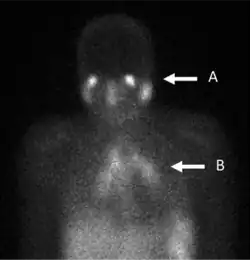

A gallium scan is a type of nuclear medicine diagnostic investigation that uses either a gallium-67 (67Ga) or gallium-68 (68Ga) radiopharmaceutical to obtain images of a specific type of tissue, or disease state of tissue. The gamma emission of gallium-67 is imaged by a gamma camera, while the positron emission of gallium-68 is imaged by positron emission tomography (PET). Gallium salts like gallium citrate and gallium nitrate may be used. The form of salt is not important, since it is the freely dissolved gallium ion Ga3+ which is active.[1] Both 67Ga and 68Ga salts have similar uptake mechanisms.[2] Radioactive gallium(III) is rapidly bound by transferrin, which then preferentially accumulates in tumors, inflammation, and both acute and chronic infection,[3][4] allowing these pathological processes to be imaged. Gallium is particularly useful in imaging osteomyelitis that involves the spine, and in imaging older and chronic infections that may be the cause of a fever of unknown origin.[5][6] Due to lack of disease specificity, imaging with radioactive gallium(III) salts or simple complexes thereof, such as 67Ga-citrate, has gradually become less important over time and is rarely used these days.

In the past, the gallium scan was the gold standard for lymphoma staging, until it was replaced by positron emission tomography (PET) using 18F-fluorodeoxyglucose (FDG).[7][8] 67Ga-citrate imaging is still used to image inflammation and chronic infections, and it still sometimes locates unsuspected tumors as it is taken up by many kinds of cancer cells in amounts that exceed those of normal tissues. Thus, an increased uptake of gallium-67 may indicate a new or old infection, an inflammatory focus from any cause, or a cancerous tumor.

In a normal scan, uptake of gallium is seen in wide range of locations which do not indicate a positive finding. These typically include soft tissues, liver, and bone. Other sites of localisation can be nasopharyngeal and lacrimal glands, breasts (particularly in lactation or pregnancy), normally healing wounds, kidneys, bladder and colon.[24]